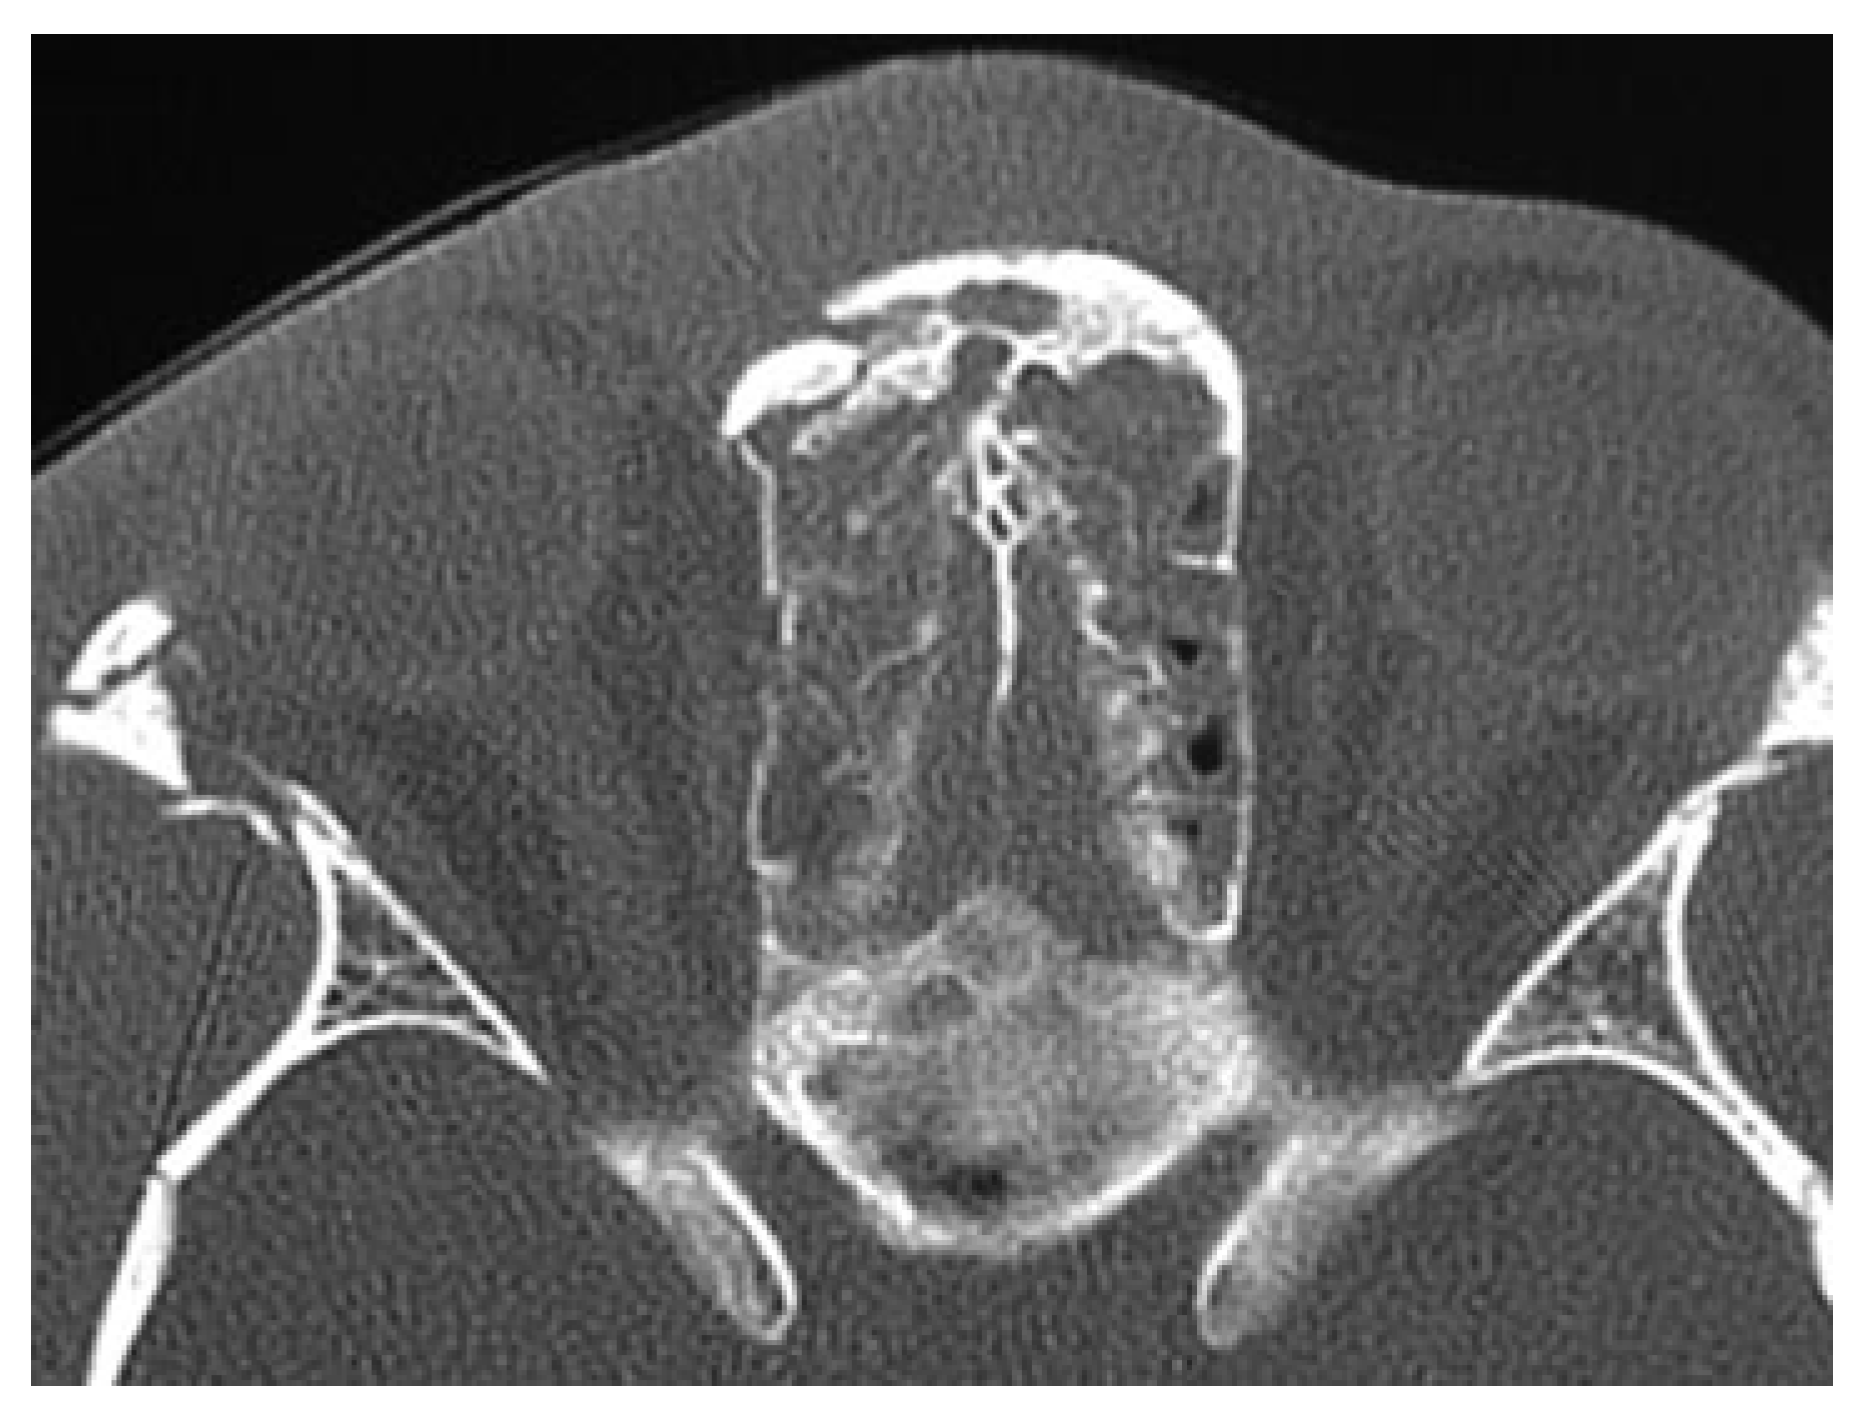

Anterior Table Fractures

Posterior Table Fractures

Nasofrontal Duct Injury